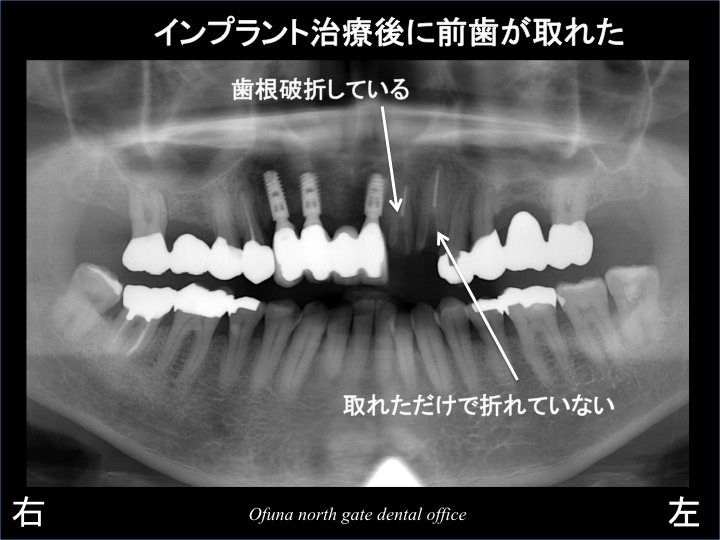

しかし、インプラント治療完了後 約1年で問題が生じました。

インプラントの左側にあった神経のない歯(中央に近い1歯のみ)が折れたのです。

その時のレントゲンが以下になります。

ただし、神経がないからといって 必ずダメになるわけではありません。

神経がない歯でも一生問題なく経過している歯もあります。